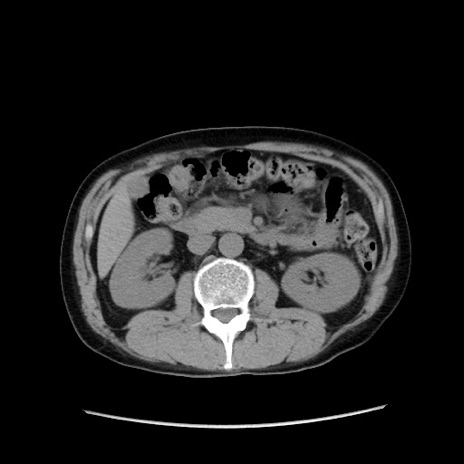

症例37(横断像)

冠状断像

【症例】40歳代 男性

【主訴】腹痛

【現病歴】4時間ほど前に電車に乗車中に臍部上より腹痛出現。徐々に増悪し起立困難となり、救急外来受診。生ものは数日食べていない。今朝お雑煮を食べた。

【身体所見】BT 36.8℃、BP 117/84mmHg、HR 91/min、SpO2 97%、苦悶様、腹部:臍上部広範囲圧痛あり、反跳痛±

【データ】WBC 8100、CRP 0.03